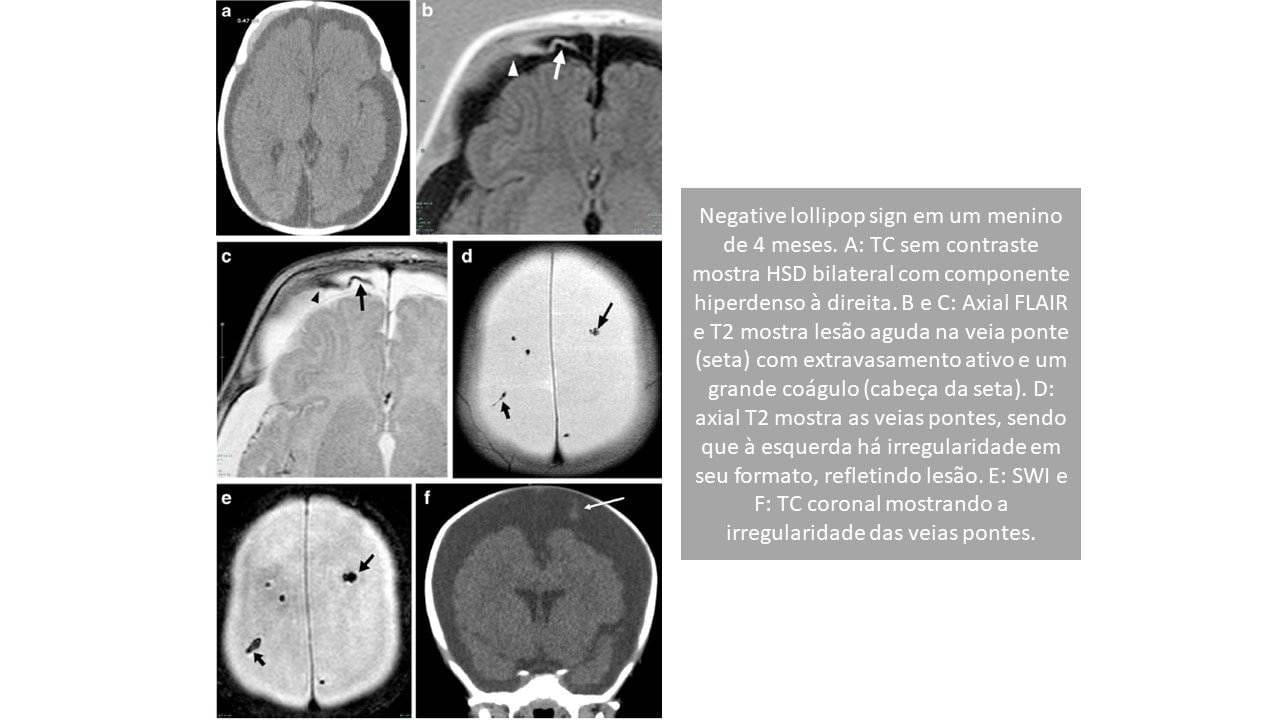

Negative lollipop sign (Sinal do pirulito negativo)

A veia ponte atravessa o coágulo de sangue e a hemorragia subdural e drena para o interior do seio (FIGURA 2). Isso pode representar uma ruptura parcial da veia ponte sem rotura completa ou ausência de lesão da veia ponte, mas com coágulo de sangue associado.